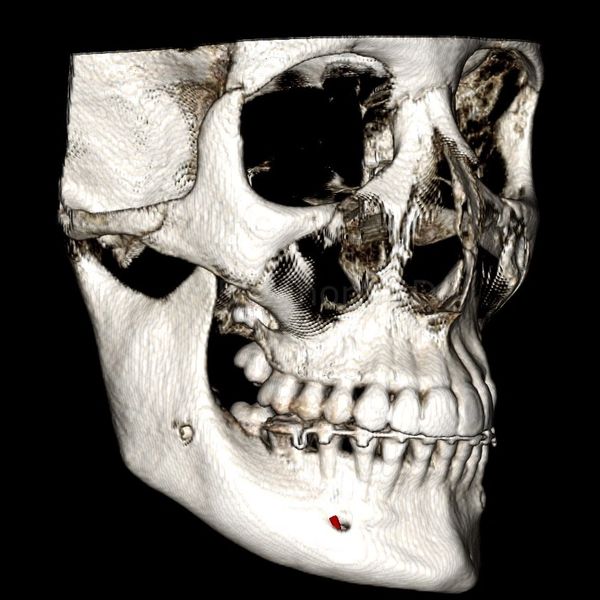

3D Side view of the Maxillofacial Skeleton